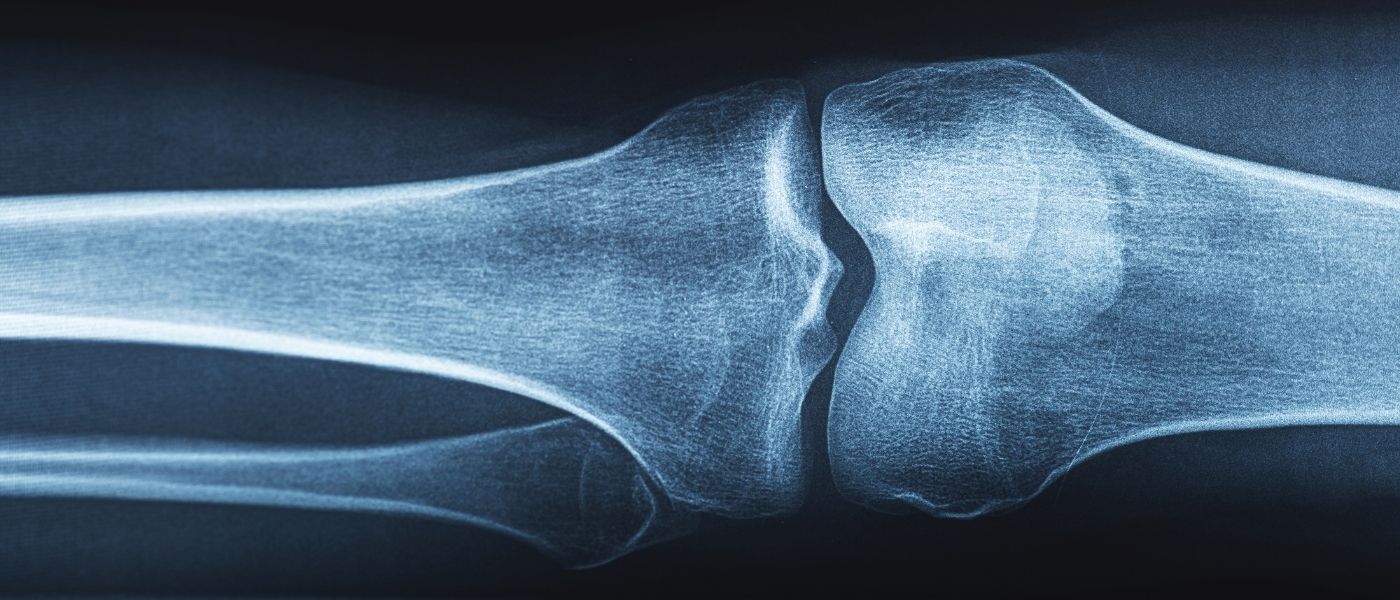

Imaging is used to rule out additional injuries or confirm severity:

- X-ray: rules out bone injuries, including small fractures. Sometimes it reveals an old MCL injury if a Pellegrini-Stieda lesion (MCL calcification) is present.